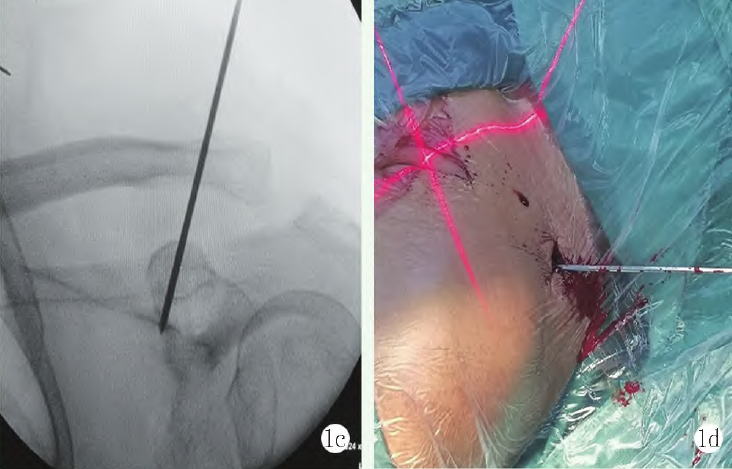

在鎖骨遠端內側大約3cm處作長約1~2cm平行鎖骨切口,切開皮膚及皮下組織顯露鎖骨骨膜。采用后交叉韌帶重建時使用的脛骨定位器械,角度調整為47°~50°,將定位器尖端扣在喙突基底部,然后放入定位套筒。此時助手幫助按壓鎖骨遠端復位,通過定位器鉆入直徑2.0mm導針(圖1b)。C 形臂X線機透視導針方向及位置滿意后(圖1c, 1d),使用直徑4.5mm空心鉆頭沿導針鉆穿鎖骨雙側皮質及喙突基底部。用可帶線導針帶牽引線從鎖骨側插入喙突側,然后在喙突側分離取出牽引線。

1c, 1d: 透視見導針方向及位置滿意